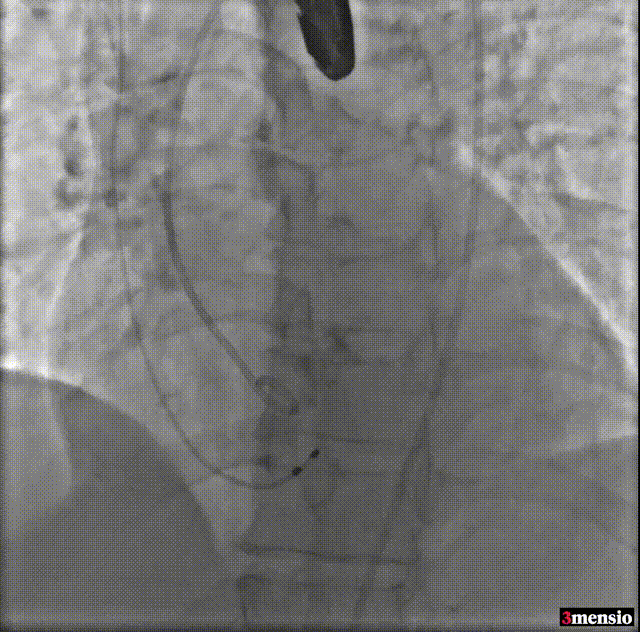

由于该病例瓣上限制较重,手术团队讨论决定使用沛嘉20mm球囊后扩处理:

球囊后扩

瓣膜最后形态造影

压差

术前压差:115mmHg

术后压差:9mmHg